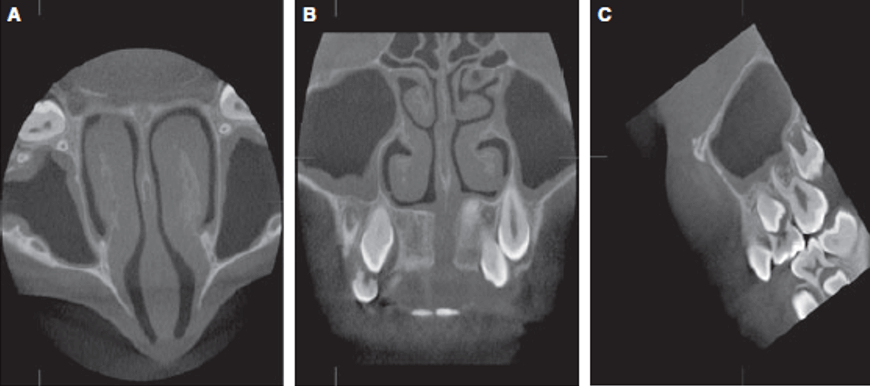

Fig.2

Este estudio muestra que incluso en imágenes TCCB con un campo de visión limitado (4 × 4 / 6 × 6 / 8 × 8 cm), los hallazgos incidentales del seno maxilar están presentes en una alta proporción (46,8 %). Por lo tanto, cuando se utilizan imágenes tridimensionales, no solo deben examinarse las reconstrucciones 3D renderizadas en superficie, sino que todos los cortes TCCB deben ser revisados sistemáticamente en las tres dimensiones (axial, coronal y sagital). Cuando hay hallazgos incidentales, deben interpretarse junto con otros especialistas para evitar la subestimación o sobreestimación de posibles patologías. Los autores fomentan el desarrollo de directrices para el uso y la interpretación de imágenes tridimensionales realizadas con fines ortodónticos.